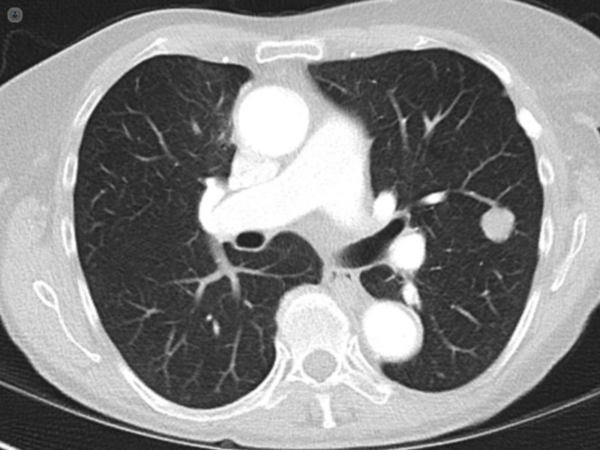

Estos nódulos pueden ser clasificados en sólidos, subsólidos con vidrio esmerilado o de consistencia mixta. La mayoría de ellos son asintomáticos y se descubren incidentalmente durante estudios de imagen realizados por otras razones. Su aspecto redondeado y aislado en el contexto de un pulmón normal sugiere que están bien delimitados y no asociados con otras anomalías pulmonares.

La evaluación de un nódulo pulmonar solitario para determinar su probabilidad de malignidad se basa en una combinación de datos clínicos y características radiográficas. La tomografía computarizada (TC) juega un papel crucial en esta evaluación debido a su capacidad para proporcionar una visión detallada del nódulo y de su entorno.

Además de la evaluación temporal, las características radiográficas del nódulo son fundamentales. El tamaño del nódulo está estrechamente relacionado con el riesgo de malignidad. Estudios han demostrado que la tasa de malignidad varía significativamente con el tamaño del nódulo, siendo mucho más alta en nódulos grandes. Para nódulos de 2 a 5 mm, la tasa de malignidad es del 1%. En nódulos de 6 a 10 mm, la tasa aumenta al 24%. Nódulos de 11 a 20 mm presentan una tasa de malignidad del 33%, mientras que nódulos de 21 a 45 mm tienen una tasa de malignidad del 80%. Este incremento en la tasa de malignidad con el tamaño sugiere que los nódulos más grandes tienen una mayor probabilidad de ser malignos.

Las características de los bordes del nódulo también son indicativas. Un borde liso y bien definido es generalmente asociado con procesos benignos, mientras que los márgenes mal definidos o lobulares sugieren una mayor probabilidad de malignidad. La presencia de márgenes espiculados y un halo periférico, observados a través de la TC de alta resolución, están altamente correlacionados con malignidad. Estos hallazgos reflejan una posible invasión del tejido circundante, un signo común de cáncer.

La calcificación del nódulo es otra característica importante para la evaluación. Las lesiones benignas suelen mostrar una calcificación densa en un patrón central o laminado, que es típico de ciertos tipos de granulomas o hamartomas. En contraste, las lesiones malignas tienden a presentar calcificación más escasa, a menudo en forma de pequeños puntos o excéntrica, lo cual es menos estructurado y puede indicar crecimiento tumoral desorganizado.

Finalmente, la presencia de lesiones cavitarias también ofrece información diagnóstica. Las cavitaciones con paredes gruesas, especialmente aquellas con un grosor mayor a 16 mm, tienen una mayor probabilidad de ser malignas. Las características de estas cavitaciones, como su grosor y contorno, son mejor evaluadas mediante TC de alta resolución en comparación con la radiografía de tórax, que puede no proporcionar suficiente detalle para una evaluación precisa. La TC de alta resolución también es superior en la detección de linfadenopatía y la presencia de múltiples lesiones, factores adicionales que pueden influir en la probabilidad de malignidad.